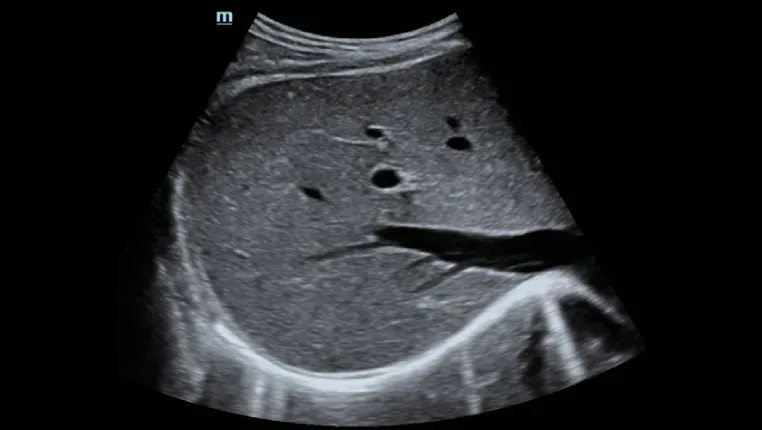

- Проводить количественное выявление и оценку фиброза и стеатоза печени под визуальным контролем 2D-ультразвука в режиме реального времени

- Позволяет избежать образования кровеносных сосудов и повреждений, повысить точность и достоверность измерения

- Значительно снижает сложность операции, повышает точность и повторяемость количественных измерений

Пункция печени под контролем ультразвука